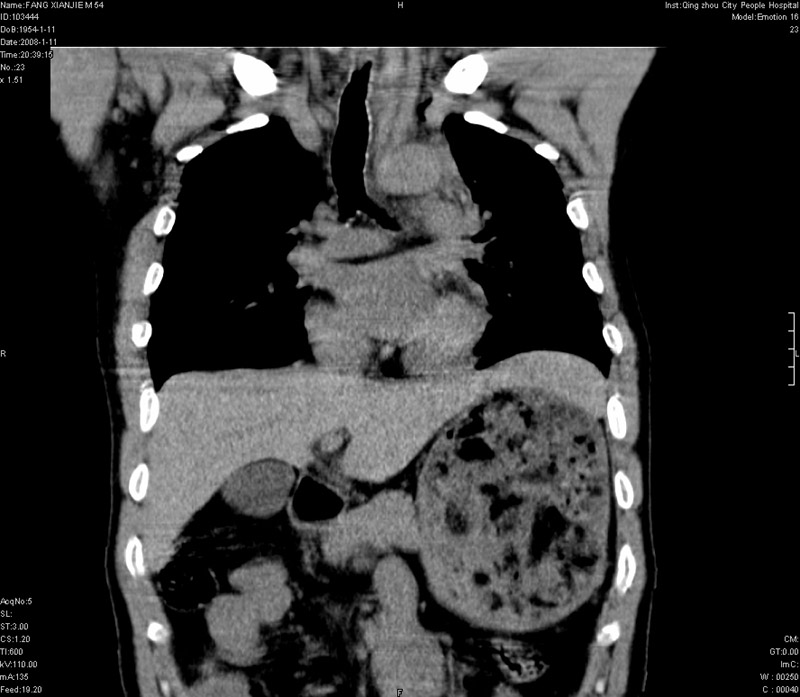

男性,40岁。胸部被车压伤伴胸痛1小时来院就诊。检查:一般情况尚可,血压110/80,胸部及上腹部压痛。结果在三天后公布。骨窗在横断位、冠矢状显示肋骨、胸椎、和胸骨未见骨折征象。

ct11308:胸部外伤1小时(证实病例) (2008-1-13 16:2)结果如下:病人入院后两小时后症状加重,8小时后在征得病人家属同意做了ct增强扫描。如下图。最终临床诊断:外伤性胸主动脉破裂并纵隔内血肿。由于有运动性伪影,胸骨在矢状面重建的图像似有骨折征,这是一种假象,我们称之为“假骨折”,这在多层ct重建中经常性遇到,必要时要结合横断图像鉴别之。现在,病人的一般情况较差,是否要手术家属尚有争议,如果手术修补,难度较大,需要专门预定制作固定支架。

以下是引用拾荒者在2008-1-16 18:46:00的发言:[br]ct11308:胸部外伤1小时(证实病例) (2008-1-13 16:2)结果如下:病人入院后两小时后症状加重,8小时后在征得病人家属同意做了ct增强扫描。如下图。最终临床诊断:外伤性胸主动脉破裂并纵隔内血肿。由于有运动性伪影,胸骨在矢状面重建的图像似有骨折征,这是一种假象,我们称之为“假骨折”,还有双侧肋骨的“假骨折”,这在多层ct重建中经常性遇到,必要时要结合横断图像鉴别之。现在,病人的一般情况较差,是否要手术家属尚有争议,如果手术修补,难度较大,需要专门预定制作固定支架。[br][br]再次表示感谢!

当然,对于该病例,其它非重要的诊断还有:右侧少量气胸;左侧胸腔积液;左侧轻度肺挫裂伤。对于纵隔内血肿,我们曾经遇到过多例,也有怀疑主动脉的破裂,但是,均未得到具体出血部位的明确诊断。